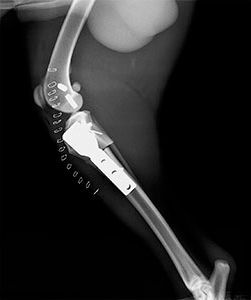

TPLO

La TPLO (Tibial Plateau Levelling Osteotomy) y la TWO (tibial wedge ostectomy) son otras técnicas de resolución de rotura de ligamento cruzado muy eficaces en perros de gran talla.

Consiste en hacer un corte en la tibia y nivelar la meseta tibial, aplicando una placa especial que hace que el ligamento cruzado no sea necesario, ya que se neutralizan la fuerzas de empuje tibial.